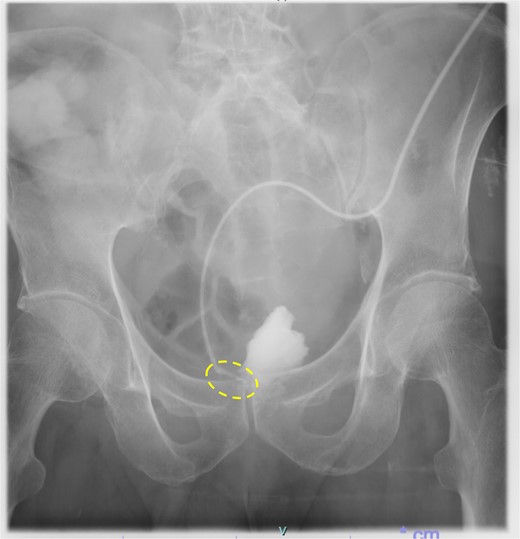

Following reoperation, although drainage led to shrinkage of the fistula, it persisted after 2 months (Fig. 2). Hence, we decided to close the fistula using endoscopic clips. Gastrografin was injected through the drain under colonoscopy and radiography, and bleeding was observed at the suspected fistula orifice, which was provisionally clipped using a MANTIS clip. Gastrografin was injected again, and definitive clipping was completed confirming the successful fistula closure (Fig. 3). The patient was discharged after 2 days. The drain was withdrawn about 3 cm on day 9 after discharge. On day 15, gastrografin injection under radiography revealed recovery of the fistula (Fig. 4). Thereafter, the drain was withdrawn cautiously about 2 cm every 2–3 days to prevent residual fistula formation and removed completely on day 29. Ileostomy closure was performed 6 months after the initial surgery. The patient was discharged without complications on postoperative day 7.

Persistence of fistula even after 2 months of re-operation (dotted circle)